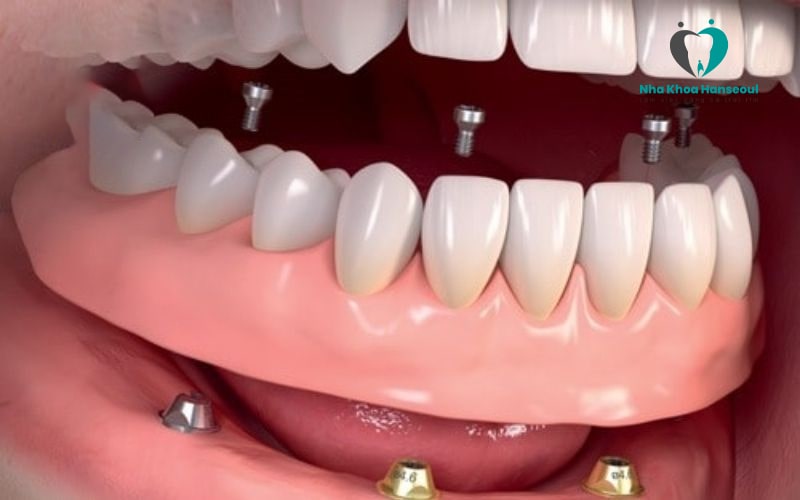

Cấy ghép Implant All On 4 là giải pháp với kỹ thuật cấy 4 trụ Implant vào xương hàm của bệnh nhân. Tuy nhiên, để sử dụng kỹ thuật này thì xương hàm của bệnh nhân phải đủ chắc chắn và đủ dày để hỗ trợ các implant được vững chắc.

Thông thường vị trí đặt trụ implant của kỹ thuật All On 4 thường là: 2 trụ đặt thẳng đứng ở nhóm răng cửa trước. 2 trụ đặt theo góc nghiêng 30 – 45 độ ở nhóm răng hàm. Tuy nhiên, vị trí đặt trụ implant không phải ai cũng giống nhau. Mỗi bệnh nhân sẽ được bác sĩ nha khoa tư vấn cụ thể, chi tiết sau khi thăm khám kỹ càng.

Sau khi cấy implant all on 4, bác sĩ sẽ sử dụng một hàm răng giả hoặc các nhịp cầu răng để phục hình lên phía trên giúp bệnh nhân thuận lợi ăn nhai.

2.4 Implant All On 6

Implant All On 6 là giải pháp cải tiến hơn all on 4 khi sử dụng 6 trụ Implant để đặt vào xương hàm bệnh nhân. Với kỹ thuật All On 6, các trụ chân răng thường được dựng thẳng đứng. Vị trí lắp đặt cũng được phân bố đều khắp cả hàm.

Kỹ thuật này được sử dụng khi xương hàm của bệnh nhân mỏng hơn hoặc không đủ chắc chắn để sử dụng phương pháp implant all on 4.